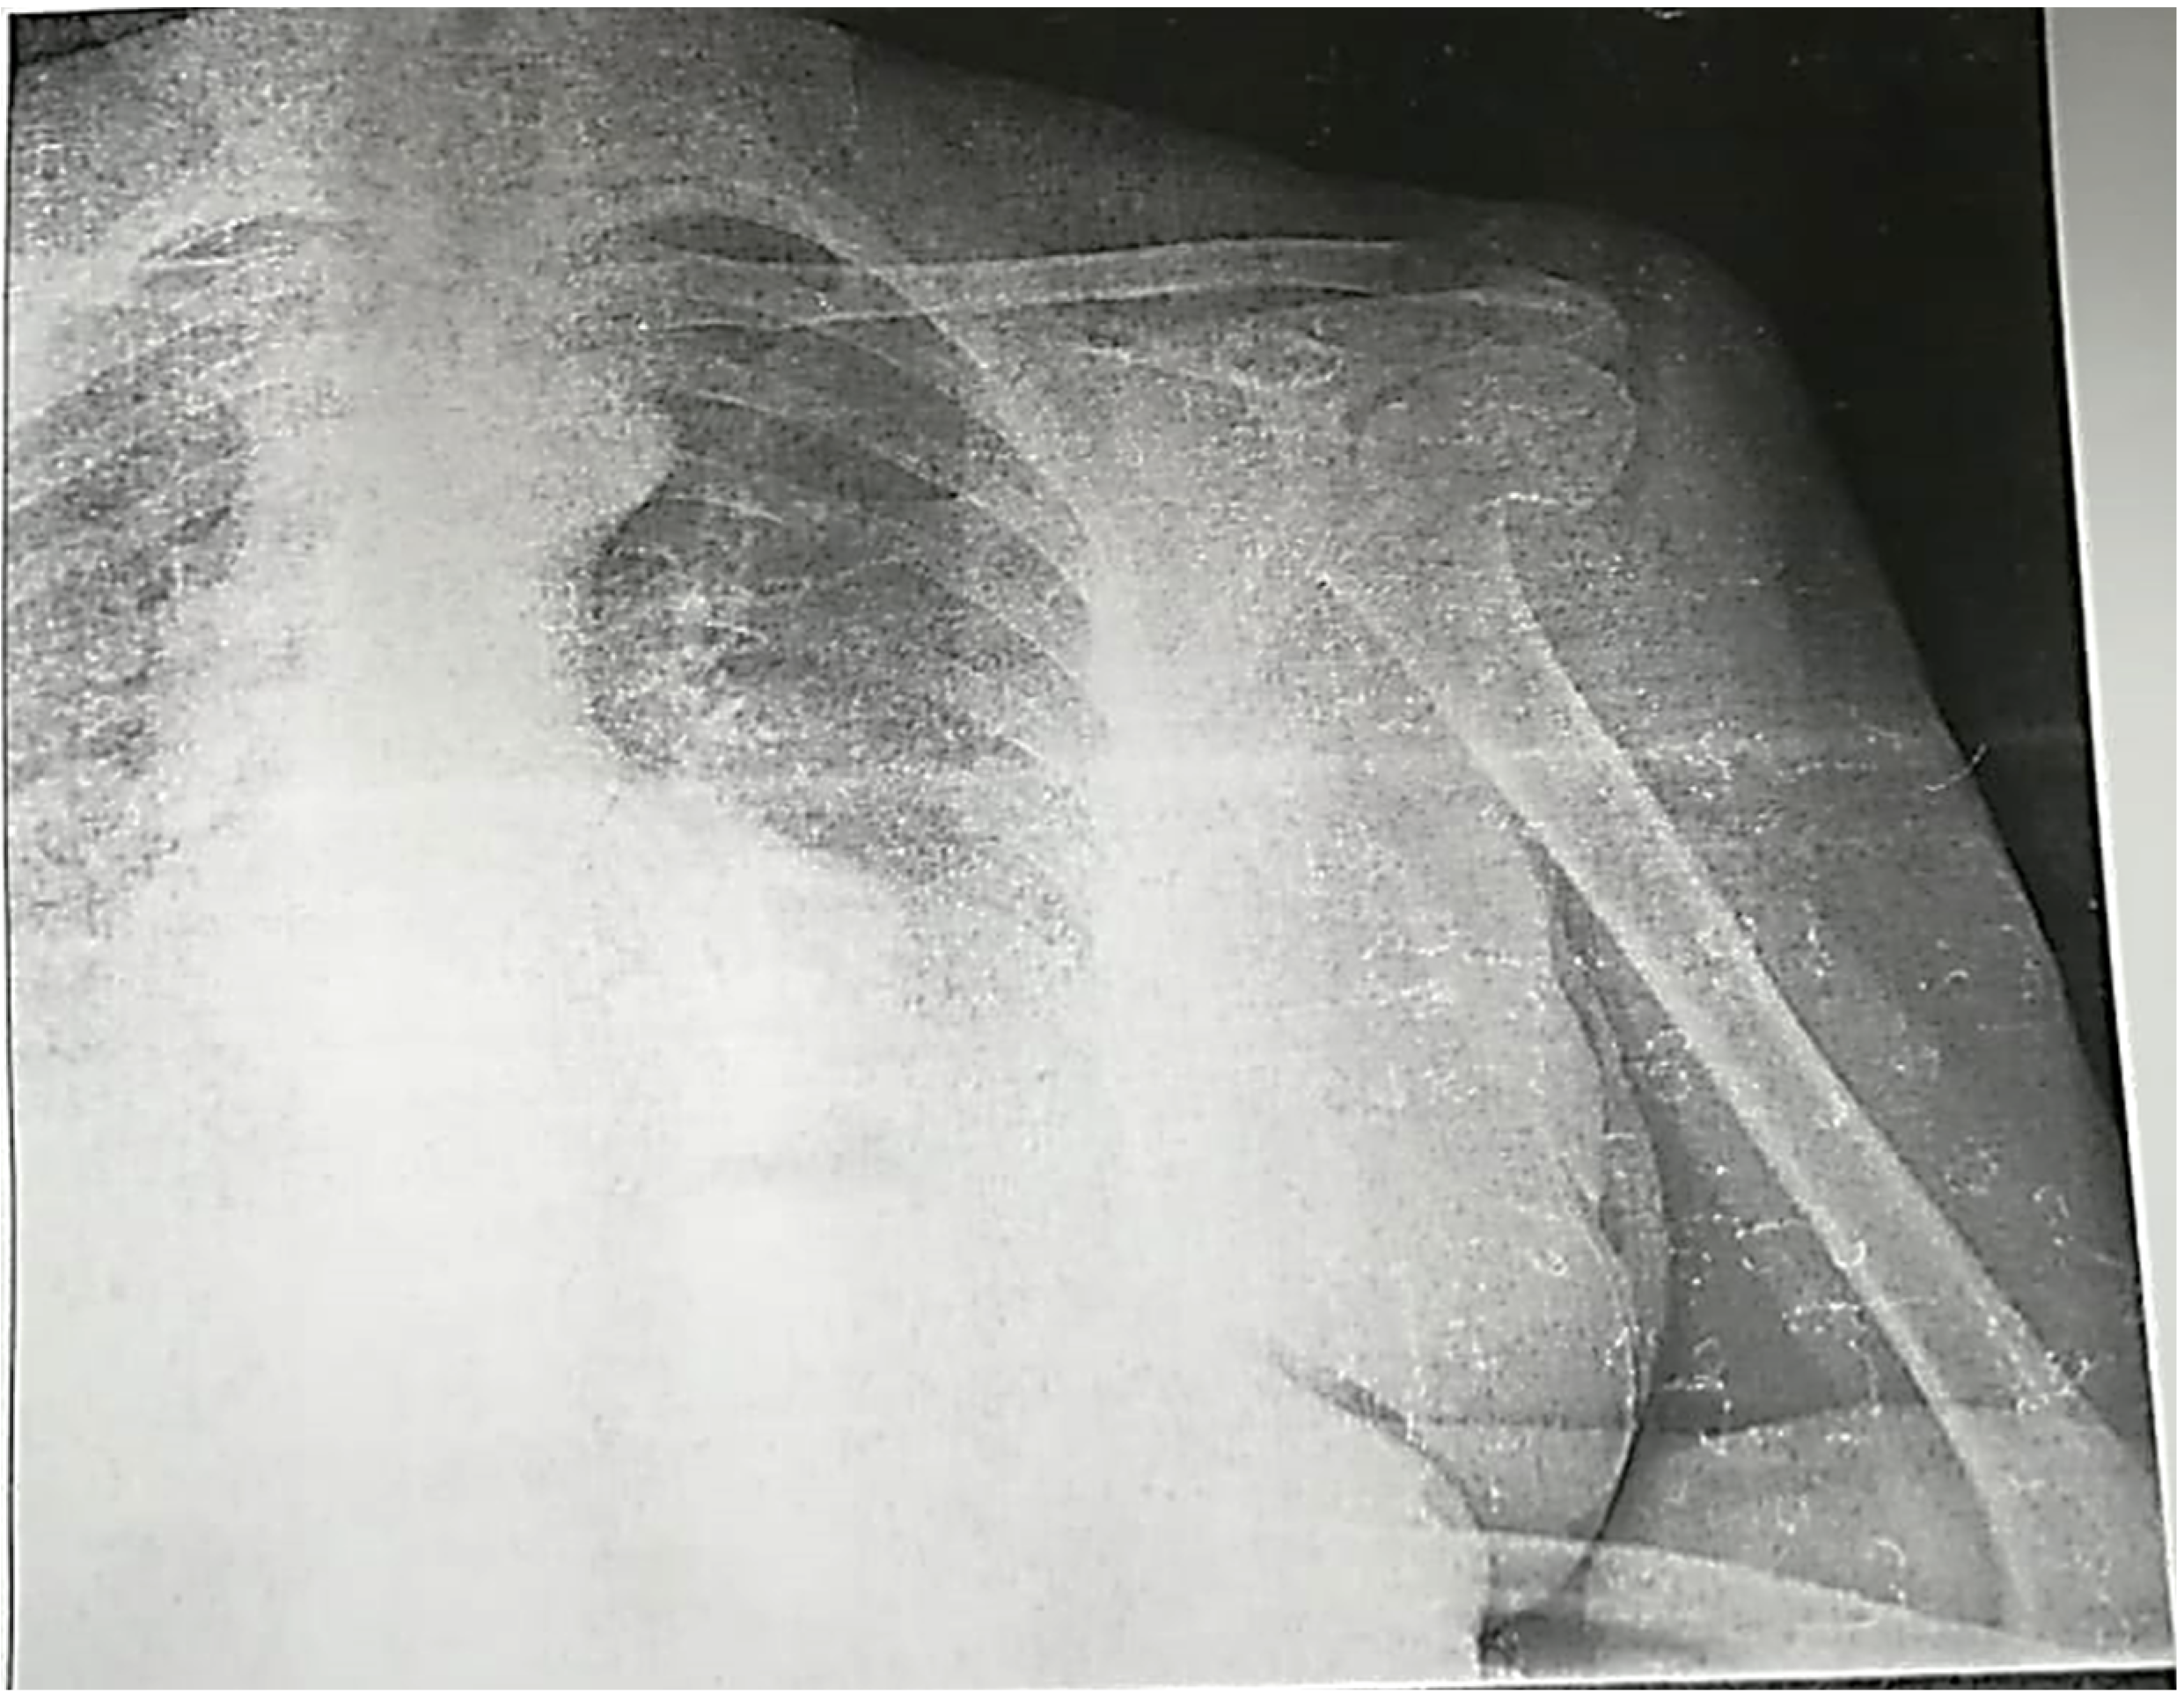

2. Case Report

2.2. Imaging Studies